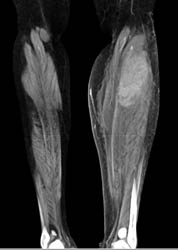

Avascular Necrosis (AVN) With Fracture